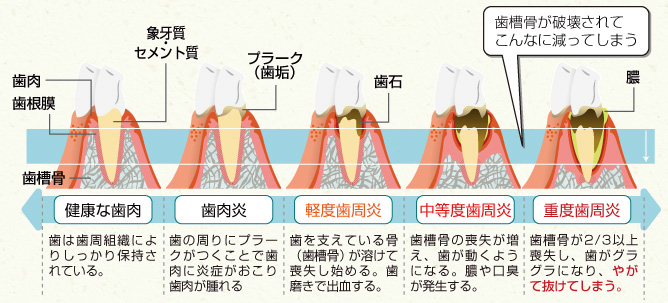

歯周病の進行の様子

歯周病は自覚症状がほとんどなく、かなり進行してから気付くことが多くなっています。進行してしまうと健康な歯を失うことになりますし、治療もかなり難しくなって次々に歯を失うことになりかねません。

歯周病は歯ぐきに炎症を起こすだけでなく、顎の骨を溶かしていく病気です。骨の減少と炎症によって歯ぐきが痩せて下がり、以前より歯が長くなったように見えることがあります。歯と歯の間も広がり、食べかすが挟まりやすくなるため虫歯リスクも上昇します。また歯が浮いたような違和感が生じることもあります。

歯を支えている骨が歯周病の原因菌によって溶かされていき、舌や指で押すと歯がグラつくようになります。歯のグラつきがある場合には、歯周病がかなり進行しており、一刻も早く適切な治療を受ける必要があります。